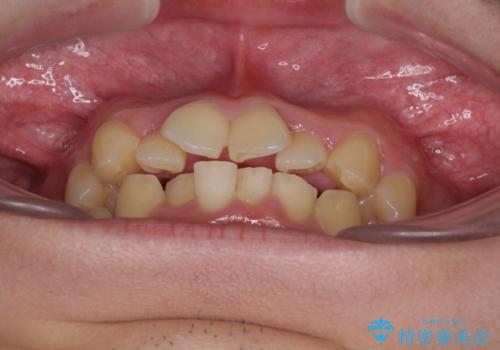

- 結婚式が近いとのことで、前歯のデコボコを改善したいと来院された患者様です。

口元の突出感はないものの、上顎前歯のデコボコが著しかったため、上顎左右第一小臼歯2本を抜歯することとしました。